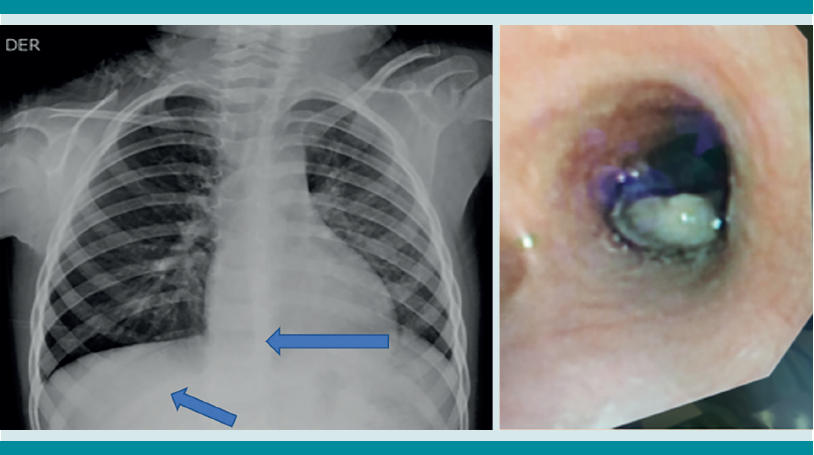

La radiografía de tórax es el primer estudio en un paciente pediátrico que llega al servicio de urgencias con sospecha de aspiración de cuerpo extraño. Gran parte de los objetos aspirados son radiolúcidos (biológicos y plásticos) y, por lo tanto, no se ven por este medio. Solo se logrará observar el cuerpo extraño en 15% de los casos (metálicos y huesos).1,6,8 Es más común identificar datos indirectos (aparecen hasta en 50% de las radiografías), que son consecuencia de la obstrucción en la vía aérea (atrapamiento de aire, atelectasias, consolidación, neumotórax) (Figuras 1,2,3,4,5). Respecto de las radiografías de tórax es que, incluso 45% pueden interpretarse normales, lo que puede resultar en un diagnóstico erróneo.1,6,9

Si al momento de consultar el paciente se encuentra en la etapa aguda, pero está estable, es decir, sin datos clínicos de inestabilidad cardiorrespiratoria, o se encuentra en la etapa oligosintomática pueden solicitarse los estudios de imagen. La radiografía de tórax es el principal recurso con el que cuentan la mayor parte de los servicios de urgencias. Es rápido, fácil, poco costoso y no requiere sedación. En caso de que sea un objeto radio-opaco, aportará el diagnóstico de manera rápida, y dará la localización del objeto (Figura 7). En caso de ser radiolúcido, la radiografía puede ser normal o mostrar los datos indirectos de obstrucción comentados. La tomografía axial computada de tórax puede considerarse si se cuenta con el recurso, tomando en cuenta lo mencionado.